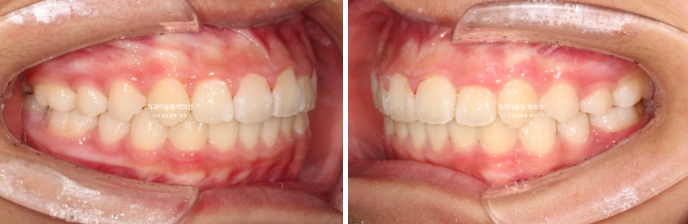

25년 5월부터 25년 7월까지 앞니배열 개선을 위해 추가장치를 짧게 낀 후 치료를 마무리 했습니다.

25.07

중심선은 잘 맞고

어금니 교합은 물샐틈 없는 1급 교합관계를 보입니다.

이제 전 후 비교해 보겠습니다.

총 치료기간은 1년 6개월이고 중간에 중심선 이슈로 잠시 쉬는 시간이 4개월 있었습니다.

재제작은 총 2회 했습니다.

24.02~25.07

치료결과가 어린이 교정이 아닌 정식 성인교정 치료 결과에 준한만큼 유지장치도 철저히 들어갑니다.

어긋난 중심선이 맞아졌으며 기울어진 앞니 치축도 좋아졌습니다.

앞니가 깊게 물리는 과개교합도 좋아졌습니다.